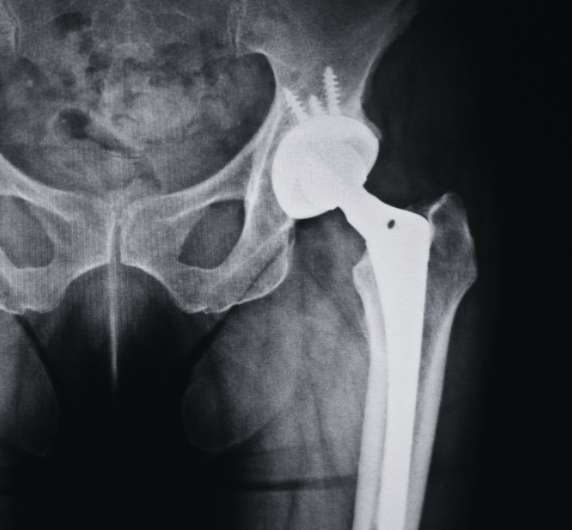

- A retrospective cohort study using a national database of over 600,000 American patients who had undergone hip or knee arthroplasty across the time period 2010 - 2021.

Total Hip Arthroplasty

Patients included:

- 32,811 with incontinence (82% females; mean age 69)

- 129,072 without incontinence (controls) (82% females; mean age 69)

Total Knee Arthroplasty

Patients included:

- 91,935 with incontinence (85% females; mean age 68)

- 367,285 without incontinence (controls) (85% females; mean age 68)

- Those with urinary incontinence had statistically higher rates of medical and joint complications following total hip arthroplasty and total knee arthroplasty. See the details in the infographic below.

- Incontinence is more common in those with medical conditions such as Multiple Sclerosis and Parkinson’s disease but remains an independent risk factor for both medical and joint complications following total hip and knee replacements.

- Screening for and attending to urinary incontinence before and after total hip and knee arthroplasty may assist in reducing post operative complications.

Those with incontinence had higher risks of joint and medical complications, particularly in females after total hip replacement. While chronic disease status is linked - incontinence is more prevalent is those with Multiple Sclerosis and Parkinson's disease - incontinence remains an independent predictor of increased post-operative complications. Pelvic floor and hip muscle function are both known to be poorer in those with incontinence, and continence and muscle function may both be influenced by hip arthroplasty.

Optimising pelvic floor and hip muscle function pre-operatively may assist in reducing complications after total hip and total knee arthoplasty. Working on continence post-operatively in an holistic approach to rehabilitation may also optimise outcomes and reduce complications. Rehabilitation professionals should screen patients pre and post arthroplasty for continence issues and include attention to continence and the pelvic floor as part of the overall management plan. Co-ordination with a Pelvic Health physiotherapist is likely to produce best results.